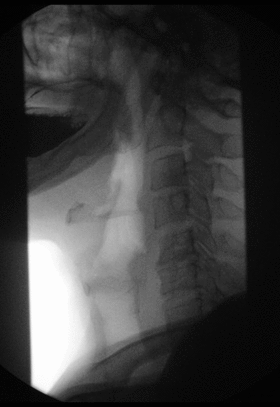

Fluoroscopy (/flʊərˈɒskəpi, flɔːr-/[1]) is an imaging technique that uses X-rays to obtain real-time moving images of the interior of an object. In its primary application of medical imaging, a fluoroscope (/ˈflʊərəˌskoʊp, ˈflɔːr-/[2][3]) allows a physician to see the internal structure and function of a patient, so that the pumping action of the heart or the motion of swallowing, for example, can be watched. This is useful for both diagnosis and therapy and occurs in general radiology, interventional radiology, and image-guided surgery. In its simplest form, a fluoroscope consists of an X-ray source and a fluorescent screen, between which a patient is placed. However, since the 1950s most fluoroscopes have included X-ray image intensifiers and cameras as well, to improve the image's visibility and make it available on a remote display screen. For many decades fluoroscopy tended to produce live pictures that were not recorded, but since the 1960s, as technology improved, recording and playback became the norm.

As the X-rays pass through the patient, they are attenuated by varying amounts as they pass through or reflect off the different tissues of the body, casting an X-ray shadow of the radiopaque tissues (such as bone tissue) on the fluorescent screen. Images on the screen are produced as the unattenuated or mildly attenuated X-rays from radiolucent tissues interact with atoms in the screen through the photoelectric effect, giving their energy to the electrons. While much of the energy given to the electrons is dissipated as heat, a fraction of it is given off as visible light.